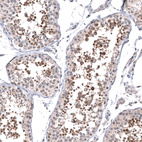

Immunohistochemistry analysis in human testis and skeletal muscle tissues using HPA007667 antibody. Corresponding MAPK13 RNA-seq data are presented for the same tissues.